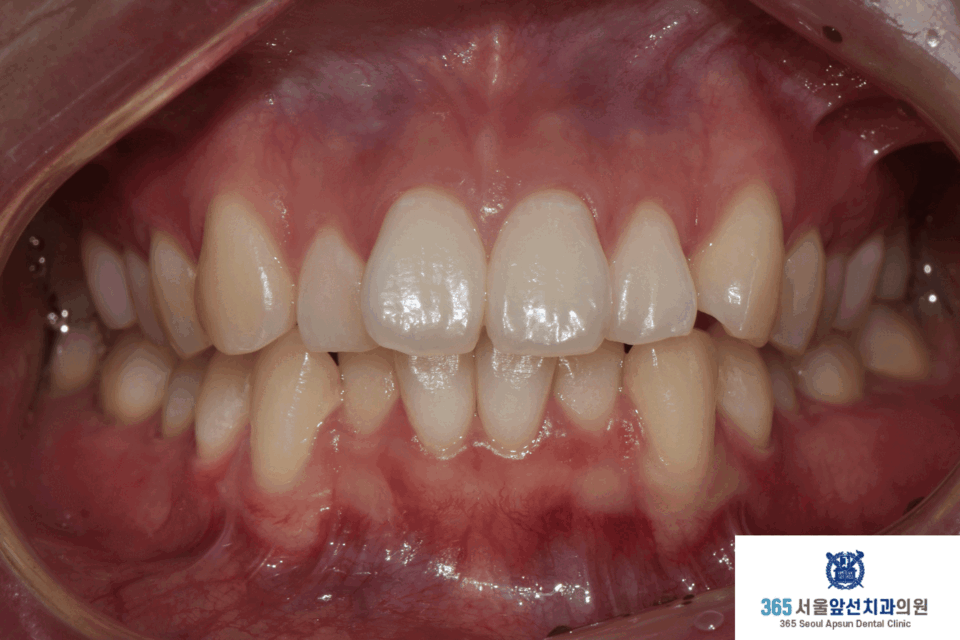

(그림1) 촬영일자 2025.02.25. / 2025.11.06.

앞니의 비뚤한 치열을 고민으로 내원하신 20대 여성 환자 분의 증례를 소개드리겠습니다. 치료 전의 모습입니다. 상,하악 치열 각각 3.1mm, 2.9mm 의 필요 공간이 있는 중등도의 총생(Crowding)이 관찰됩니다. (그림2) 촬영일자 2025.02.25.